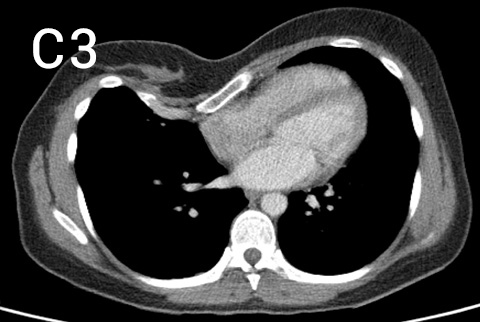

Pre-operative photos (A and B) with chest CT (C, multiple slices of upper (1), middle (2) and lower (3) chest) showing a long very asymmetrical pectus excavatum deformity in a 35 year old patient with striking symptoms of constrictive feeling in her chest